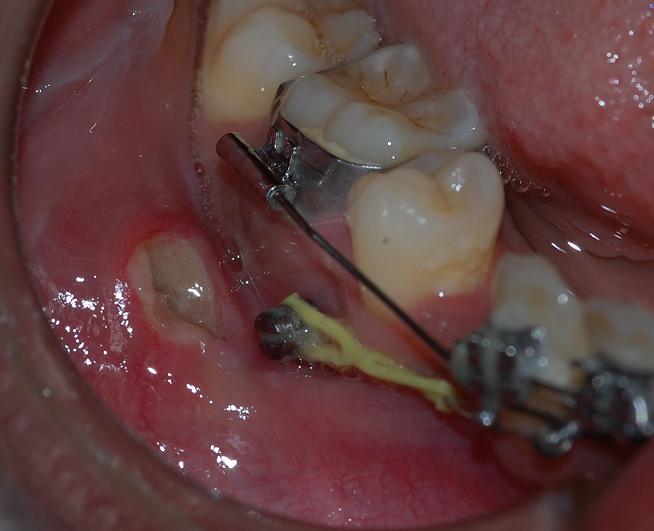

Here you can see a case where screw went into perio space and caused mesial movement of premolar, it was removed and replaced in the

same visit. Radiograph did not show any anomany and treatment continued unhindered.

Here you can see a case where screw went into perio space and caused mesial movement of premolar, it was removed and replaced in the

same visit. Radiograph did not show any anomany and treatment continued unhindered.